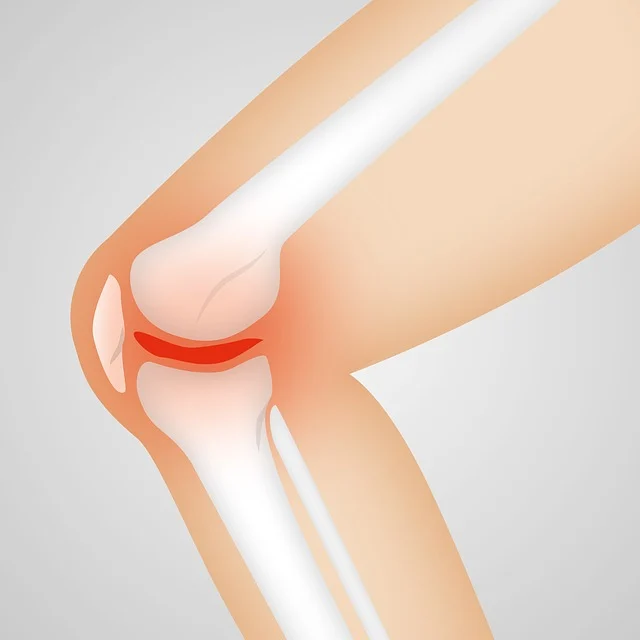

- 인공관절은 망가진 무릎 관절의 관절면, 연골, 연골판, 인대 등을 제거하고 금속의 보형물로 대체

해서 통증의 감소와 기능의 회복을 하기 위해 제공되는 보형물입니다.

퇴행성관절염 증상.

- 통증은 퇴행성관절염의 대표적인 증상입니다.

- 무릎에 물이 차는 증상, 붓기도 합니다.

- 퇴행성 관절염의 심화.

- 다리 모양의 변형 및 통증.

- 보행장애.

- 관절의 구축.